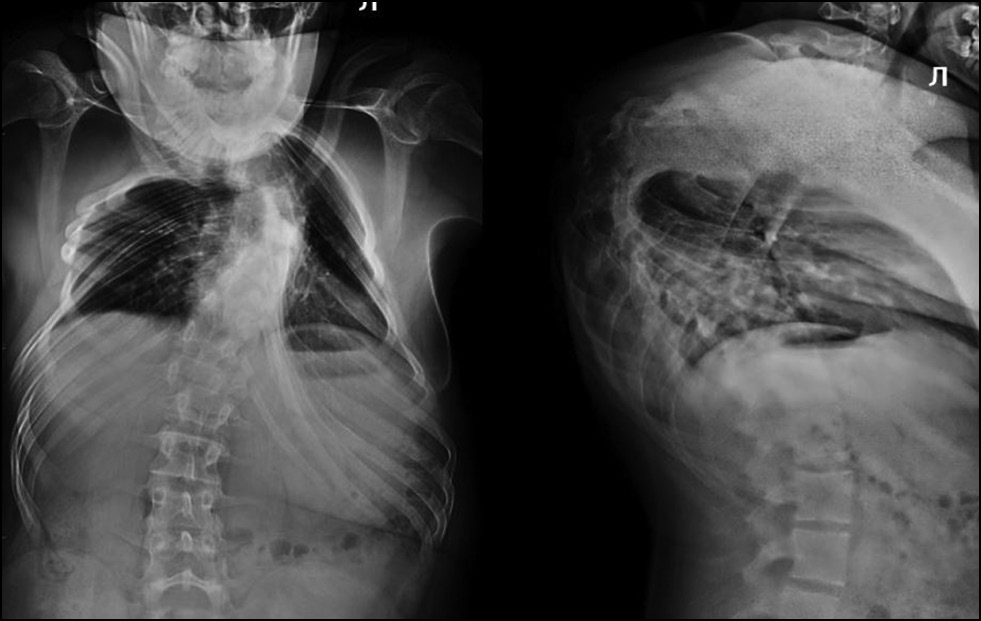

Пациенту выполнены диагностические исследования: компьютерная томография (КТ), магнитно-резонансная томография (МРТ) и рентгенограмма шейно-грудного отдела позвоночника (в прямой и боковой проекции) (рис. 1).

Рис. 1. Компьютерная томография (a), магнитно-резонансная томография (b) и рентгенограмма (c) шейно-грудного отдела позвоночника. По данным КТ и МРТ выявлен стеноз позвоночного канала С4–Тh4 с МР-признаками миелопатии. По данным КТ и рентгенографии позвоночника картина врождённой аномалии позвоночника следующая: заднебоковой клиновидный добавочный полупозвонок С7, локальный угловой кифоз на уровне С6–7 позвонка с наличием костного блока тел и задних элементов Th1–3 позвонков и заднебоковым клиновидным полупозвонком Th4–Th5.

Fig. 1. Computed tomography (a), magnetic resonance imaging (b) and radiograph (c) of the cervicothoracic spine. CT and MRI data revealed stenosis of the C4–Th4 spinal canal with MR signs of myelopathy. According to CT and radiography of the spine, the picture of the congenital anomaly of the spine is as follows: posterolateral wedge-shaped accessory hemivertebra C7, local angular kyphosis at the level of the C6–7 vertebra with the presence of a bone block of the bodies and posterior elements of the Th1–3 vertebrae and a posterolateral wedge-shaped hemivertebra Th4–Th5.

На основании клинико-лучевых методов обследования (см. рис. 1) установлен диагноз: аномалия развития шейно-грудного отдела позвоночника. Врождённый кифосколиоз шейно-грудного отдела позвоночника IV степени. Стеноз позвоночного канала с передней компрессией спинного мозга на уровне С7–Тh1. Грудная миелопатия. Верхний смешанный дистальный парапарез, нижний спастический парапарез. Нарушение функции тазовых органов (группа С по Frankel, Ashworth 3, ASIA — движение 82, тактильная 86, болевая 84).